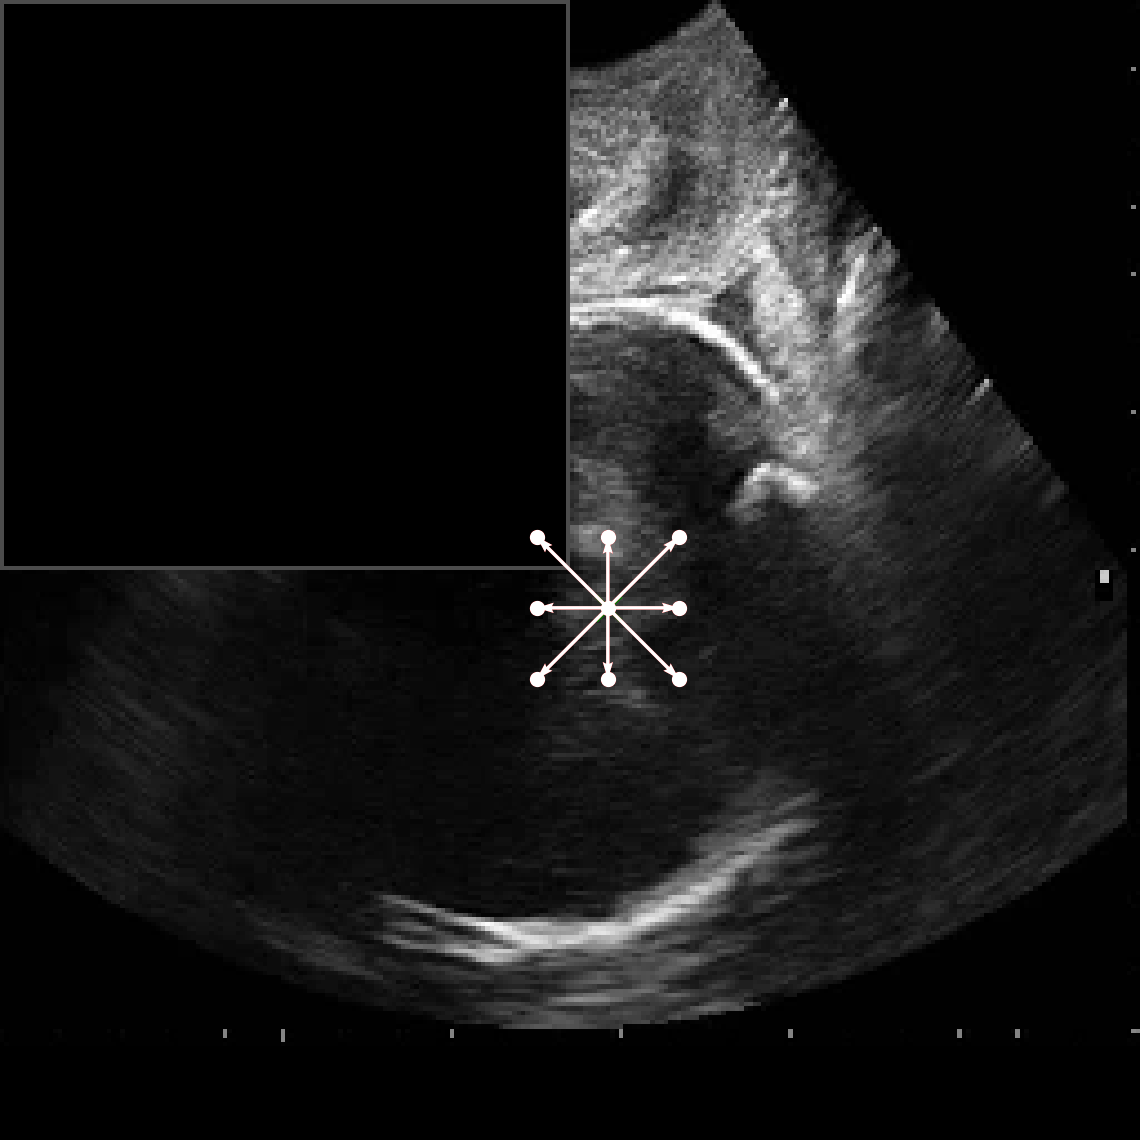

In practical clinical settings, medical images are often incomplete or degraded due to occlusions, artifacts, or limited fields-of-view. Therefore, a reliable segmentation model must be robust to missing spatial context and capable of inferring anatomical structures from partially observed inputs. To evaluate this critical property, we conducted a masking experiment using the FH-PS-AoP dataset. In this experiment, we systematically removed one quadrant from the input image, top-left, top-right, bottom-left, or bottom-right, and evaluated the performance of DAUNet compared to the baseline UNet.

Figure 7 presents a comprehensive visual comparison of the predicted offset maps and segmentation masks under each masking condition. The first column shows the original (unmasked) input along with its corresponding predictions, while subsequent columns depict the results for each of the masked quadrants.

DAUNet demonstrates markedly higher resilience to missing context compared to UNet. Its predicted offset maps remain dense and structured, with vectors that preserve anatomical directionality even when significant regions of the input are absent. This behavior reflects DAUNet’s ability to infer context from the remaining visual cues. In contrast, UNet exhibits sparse or disoriented offsets in the masked scenarios, indicating reduced spatial awareness and compromised localization.

To better understand this phenomenon, we analyzed the receptive fields of both models. For a representative pixel, we visualized its corresponding receptive area contributing to the output. In UNet, the receptive field is fixed and grid-constrained (refer to second row of Figure 7), making it sensitive to occlusions. On the other hand, DAUNet leverages deformable convolutions to dynamically adjust its receptive field based on the visible content. This adaptability is evident in the red and white arrows in the fourth column of Figure 7, where DAUNet modifies its offset patterns to account for the masked input.

The segmentation masks in third and fifth rows of Figure 7, further substantiate these findings. DAUNet consistently produces anatomically plausible segmentations of both the fetal head (green) and pubic symphysis (red), with minimal degradation even under 25% missing input. The output contours remain smooth, accurate, and well-aligned with ground truth boundaries. In contrast, UNet’s performance deteriorates noticeably, with fragmented or distorted segmentations, especially around the fetal head, as indicated by white arrows in the figure.

These results highlight the efficacy of DAUNet’s architectural innovations. The proposed combination of deformable convolution and SimAM attention allows the model to effectively reason over the visible context and compensate for spatial omissions. This robustness to incomplete inputs makes DAUNet well-suited for deployment in real-world medical environments, where noise, occlusions, and partial data are common challenges.